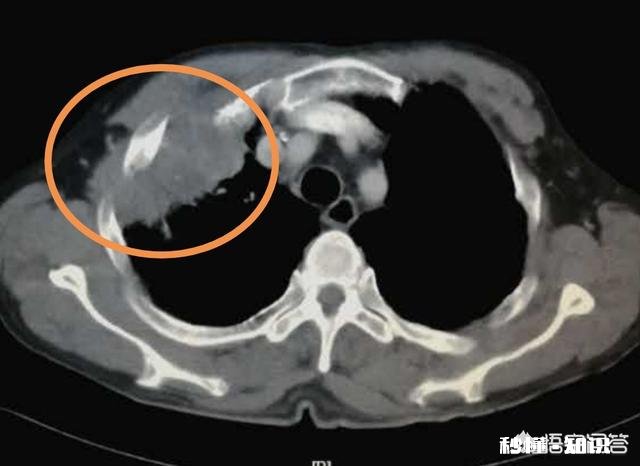

文章插图

这位病人是未分化性大细胞癌,对保守治疗不敏感 , 手术切除后半年,发生脑转移去世了 。